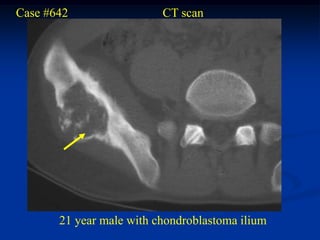

Case #642                 CT scan

21 year male with chondroblastoma ilium

Another CT cut

tumor

T-2 MRI